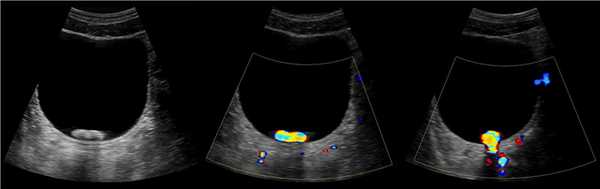

Уретероцеле на УЗИ

Исследование проводят при наполненном мочевом пузыре. Используют конвексный датчик 3,5-5 МГц. Смотри УЗИ мочевого пузыря (лекция на Диагностере).

На УЗИ в мочевом пузыре или в уретре определяется анэхогенное образование, округлой формы, с четким и ровным контуром; соответствующий мочеточник обычно заметно расширен; может присутствовать гидронефроз верхней части удвоенной почки. Уретероцеле определяют как внутрипузырные (полностью внутри мочевого пузыря) или внепузырные (некоторая часть постоянно расположена в шейке мочевого пузыря или в уретре).

Рисунок. Внутрипузырный (1) и внепузырный (2) уретероцеле.

Рисунок. Двустороннее уретероцеле на УЗИ: в режиме ЦДК из верхушек уретероцеле определяется выброс мочи.